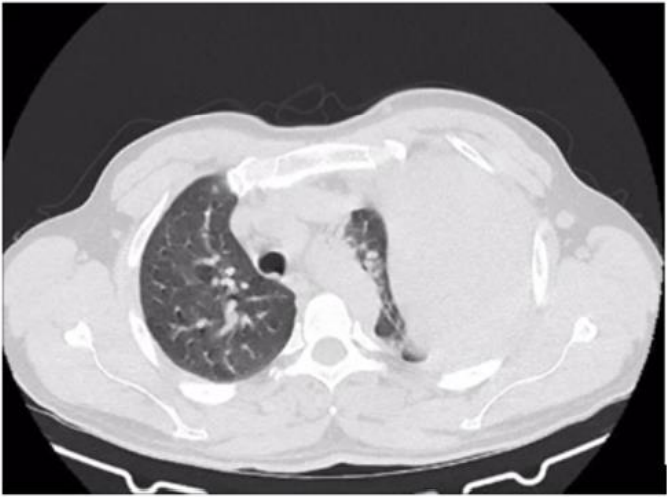

Image 3: Axial section of the pulmonary window showing displacement of the trachea and involvement of the left hemithorax due to a tumor lesion.

A percutaneous biopsy was performed with a pathological report of a lung mass with low-grade spindle cell neoplasia involving desmoid fibromatosis. Additionally, immuno-histo chemical markers were requested, which reported: solitary fibrous tumor spindle cell neoplasia vs desmoid fibromatosis. A CT angiography was performed, which showed vascularization of the lesion, predominantly of the left internal mammary artery and the ipsilateral inferior phrenic artery. The lesion is susceptible to pre-surgical embolization to reduce intraoperative bleeding. Based on the reports, an evaluation was requested by the oncology service, who

suggested surgical treatment for the T4N0M0 G1 STAGE 1B lesion, and an evaluation by interventional radiology, who performed embolization.